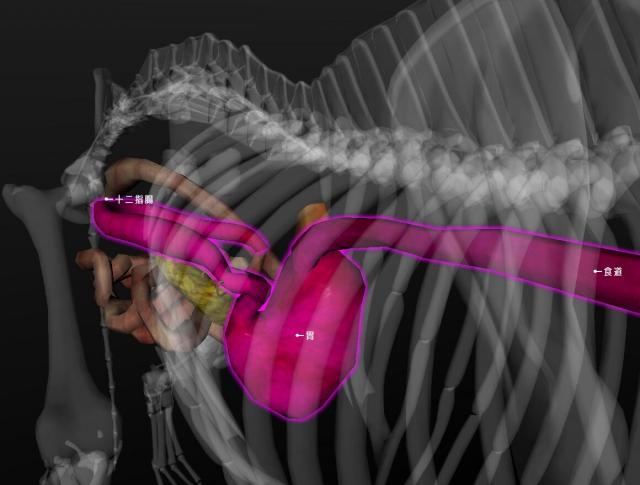

正常犬的食道、胃、十二指肠的形态与位置 |

文件来源:吴礼平

胃扭转为一种胃幽门和贲门呈纵轴从右向左顺时针扭转,挤压于肝脏、食道的末端和胃底之间,导致胃内容物不能后送的疾病。胃扭转之后很快发生胃扩张。

从后向前方看,在食管末端的胃沿顺时针方向可旋转90°~360°,这种旋转使幽门偏向中线的左侧,使十二指肠进入食管末端和胃之间。根据不同的扭转程度,脾脏可能在不同的位置从腹腔左前部到达后部。当胃扭转大于180°时,会使贲门闭塞。